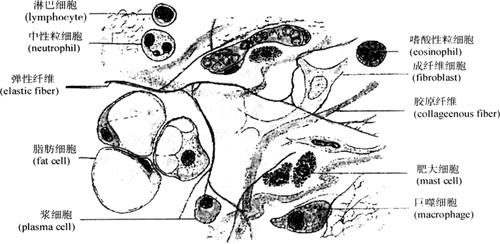

疏松结缔组织(loose connective tissue)又称小房组织(蜂窝组织,areolar tissue),广泛分布于器官与器官之间,组织与组织之间,以及细胞与细胞之间。含有丰富的血管。由血液运送的养料和代谢废物都通过毛细血管周围的结缔组织进行扩散,经上皮进入机体的外来物质(如细菌等)也必须经过其传送和其中各种细胞的识别。因此疏松结缔组织除有连接、支持作用外,还有传送营养物质、代谢产物和防御等功能。疏松结缔组织的结构特点是细胞种类多,散在分布,纤维排列稀疏而排列方向不一,具有丰富的基质(图2-21)。疏松结缔组织也是由细胞和细胞间质组成,简列如下:

图2-21 疏松结缔组织模式图

1.细胞 疏松结缔组织内的多种细胞,反映出其组织的功能特点,包括有成纤维细胞(纤维母细胞)、巨噬细胞、肥大细胞、浆细胞、脂肪细胞、未分化间充质细胞和游走性白细胞(即可针对特殊刺激而自血液中移行到组织的细胞,如淋巴细胞、嗜酸性粒细胞等)(图2-22、图2-23)。